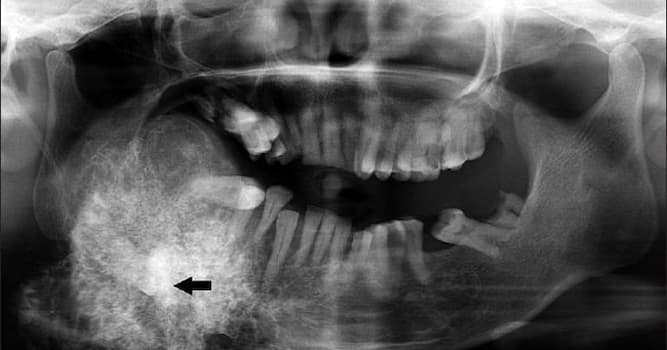

What is another name for Pindborg tumor?